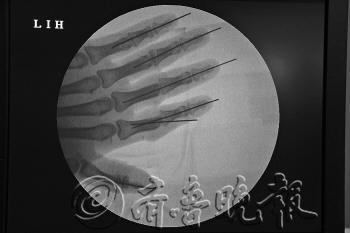

袁某的左手X光照。图片由医院提供

“断指能不能接活,缝合血管很重要。”郝丽文告诉记者,每根手指至少有5-6根血管、2条神经、3根肌腱,要接活十根手指,就需要缝合五六十根血管、20条神经、30根肌腱。“另外,还需要接骨头。”

由于血管和神经很细,手术要在显微镜下进行。为了在最短的时间内将袁某的断指接好,医院的王增涛主任挑选了科室水平最好的6名医生,两个人一组,争分夺秒,同时对左手和右手进行手术。另外两人随时顶替,轮流“左右开弓”。

从大拇指开始,两组医生几乎同时进行手术,固定骨头,把肌腱接上,缝合血管、神经。“接完后,再缝皮,每根手指的再植平均需要三个小时。”郝丽文说,其中缝合血管的难度最大,也耗时最长。